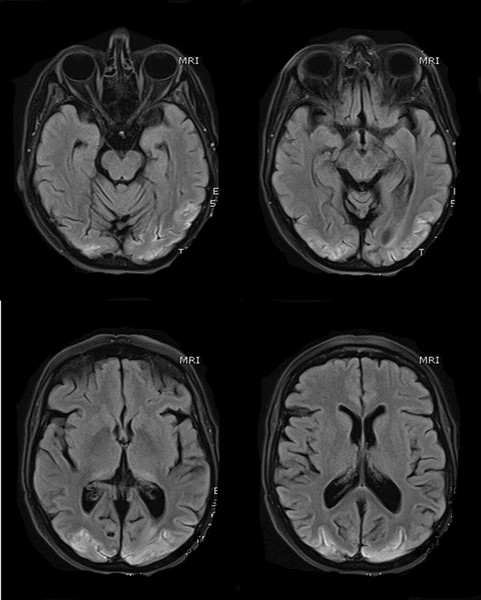

МРТ головного мозку: двостороння симетрична гіперінтенсивність кори потиличних часток.

Джерело: Cureus.com

Унаслідок було виявлено запалення в мозку: у пацієнтки виявили синдром задньої оборотної енцефалопатії (PRES). Інші назви: "гіпертензивна енцефалопатія", "синдром оборотного заднього церебрального набряку" і "задня оборотна лейкоенцефалопатія".

І лише через тиждень після проведення КТ з'ясувалося, що у хворої коркова сліпота — захворювання, викликане ураженням потиличної частки головного мозку і супроводжується повною відсутністю зору: "Водночас реакція зіниць на світло була нормальною, а очне дно було без змін".